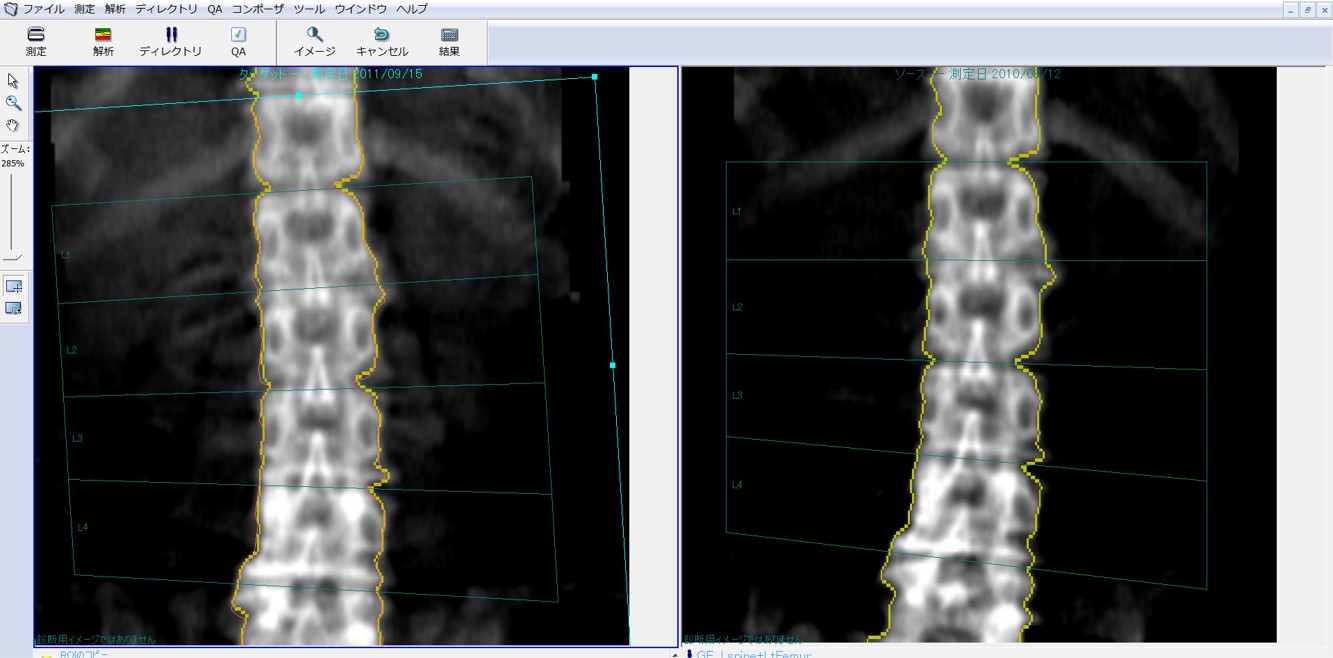

患者のポジショニングが適切でない場合、再測定が必要となります。経過観察においては、初回測定結果の情報を基本とし、関心領域(Region of interest=ROI)のサイズと部位は統一するよう心がけましょう。比較解析機能(コピーROI)を使用することにより、前回と同じ部位でのコピーROIの有用性は確立されています(図1)。この比較解析機能を使用することで、各椎体の椎間が認識しにくい症例でも、前回と同様の領域で解析が可能で、各椎体の誤認も防げます。体位の違いでうまく比較解析が利用できない場合は手動で補正します。

ClinicalTips03_02.jpg

図1. 比較解析機能